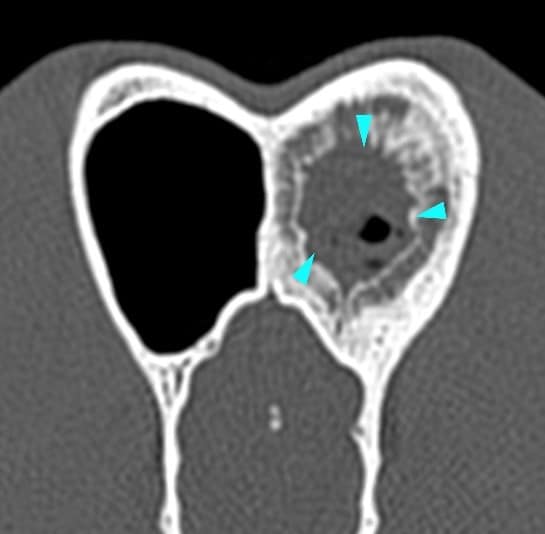

A large amount of fluid was occupying the caudal aspect of the left nasal cavity (yellow arrowheads). There was no lysis of the nasal septum, vomerine groove, ethmoid bone or cribriform plate. The left frontal sinus contained a large amount of fluid-attenuating material, surrounded by a severe ‘lamellar’ periosteal reaction (blue arrowheads).

A final diagnosis of fungal rhinitis (aspergillosis) was made.